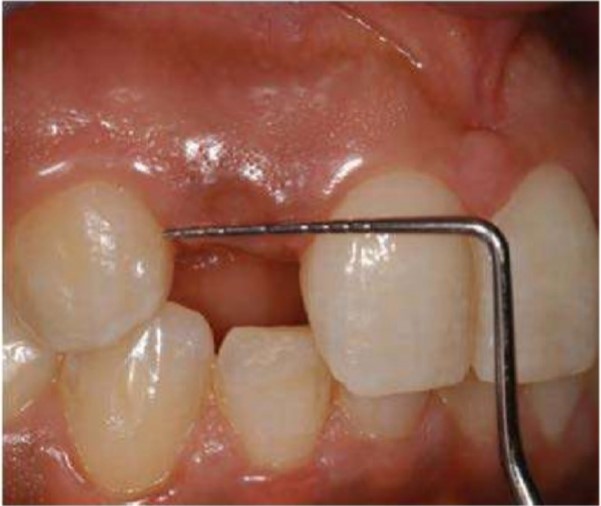

Đo khoảng mất răng bằng cây đo túi hoặc compa. Đo khoảng cách nhỏ nhất giữa 2 thân răng ngay vị trí mô mềm rất quan trọng. Có thể đo trên phim để bổ sung vào đánh giá lâm sàng.

Đo khoảng trống mất răng ngang mức thân răng quan trọng đối với vấn đề thẩm mỹ và được đánh giá bằng việc so sánh chiều rộng khoảng mất răng với răng bên cạnh nếu có. Khoảng cách giữa hai chân răng kế khoảng mất răng sẽ quyết định khi đặt implant và abutment có xâm phạm chân răng và mô mềm kế cận hay không. Khoảng cách tối thiểu thường là 6mm, cả chiều gần xa và trong ngoài. Điều này cho phép một implant đường kính 4mm có 1mm viền xương xung quanh. Nếu có một khoảng không gian đầy đủ xung quanh mão phục hình trên implant và abutment thì mô mềm và mộ bám dính răng kế cận sẽ khỏe mạnh. Chiều gần xa thường thiếu ở vùng răng cửa bên hàm trên và răng cửa hàm dưới nơi mà răng tự nhiên nhỏ.